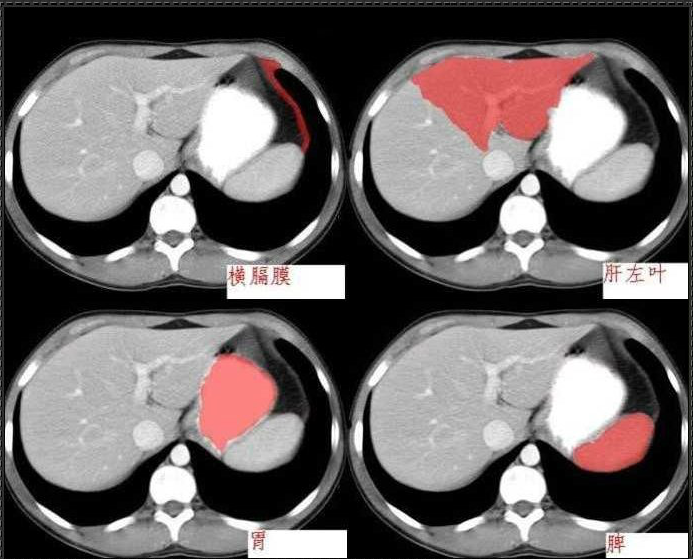

十分钟学会腹部CT解剖(多图)